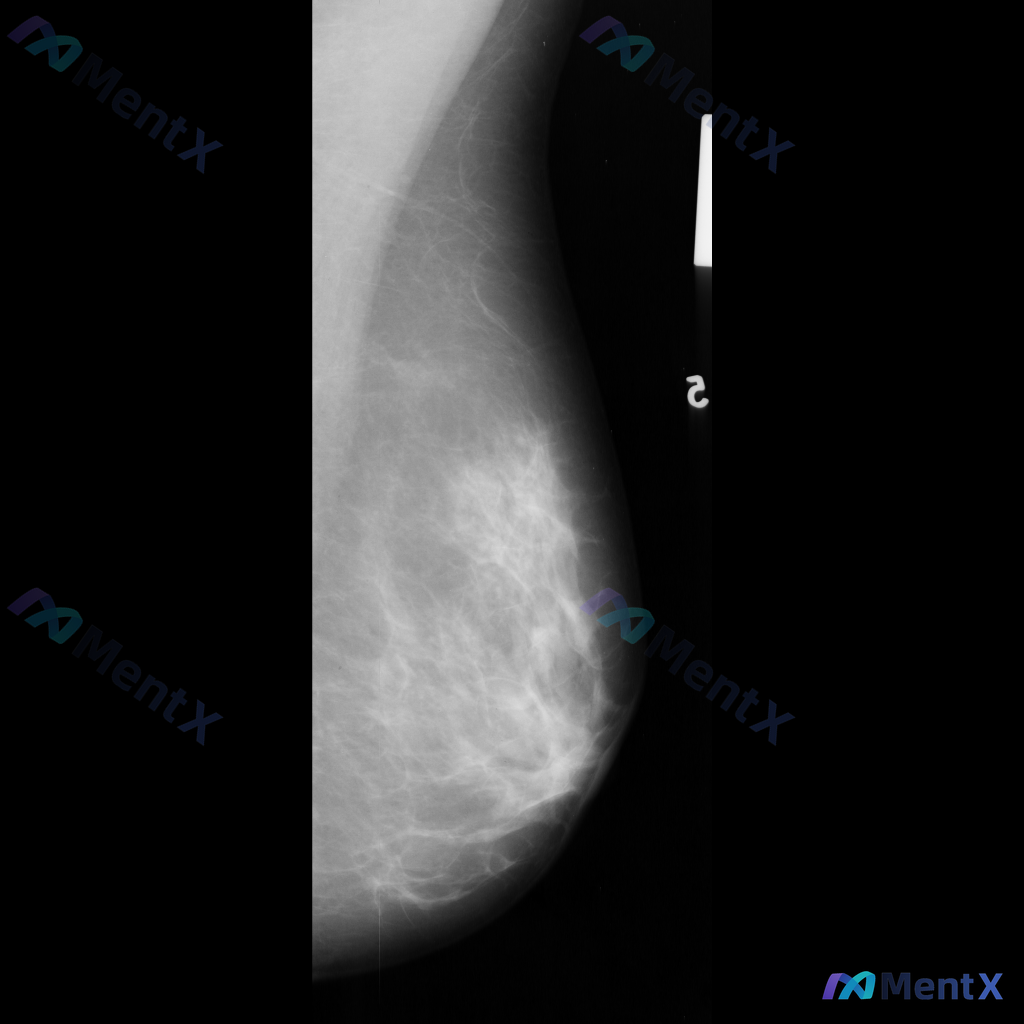

整理到一张乳腺钼靶影像的读片资料: - 影像类型:单侧乳腺MLO位 - 乳腺背景:不均匀致密型 - 主要发现:左乳下方(近胸壁侧,乳头下/后方区域)可见一局限性高密度影,边界部分清晰、部分模糊,在背景中较为突出 - 当前其他信息:未提供CC位影像及超声、MRI等补充检查 单看这组资料,大家对这个异常...